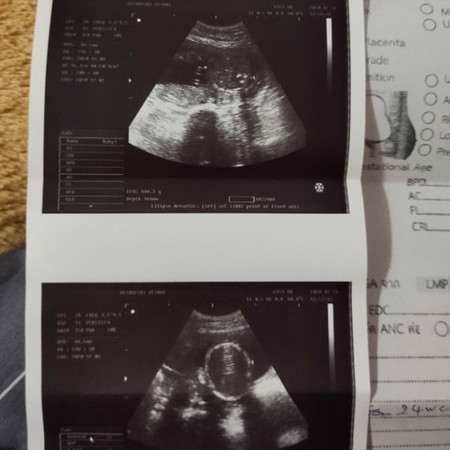

24สัปดาห์แล้วน้องยังไม่ให้ดูเลยว่าหญิงหรือชาย

จะให้ลุ้นอีกนานแค่ไหนกันลูกกก